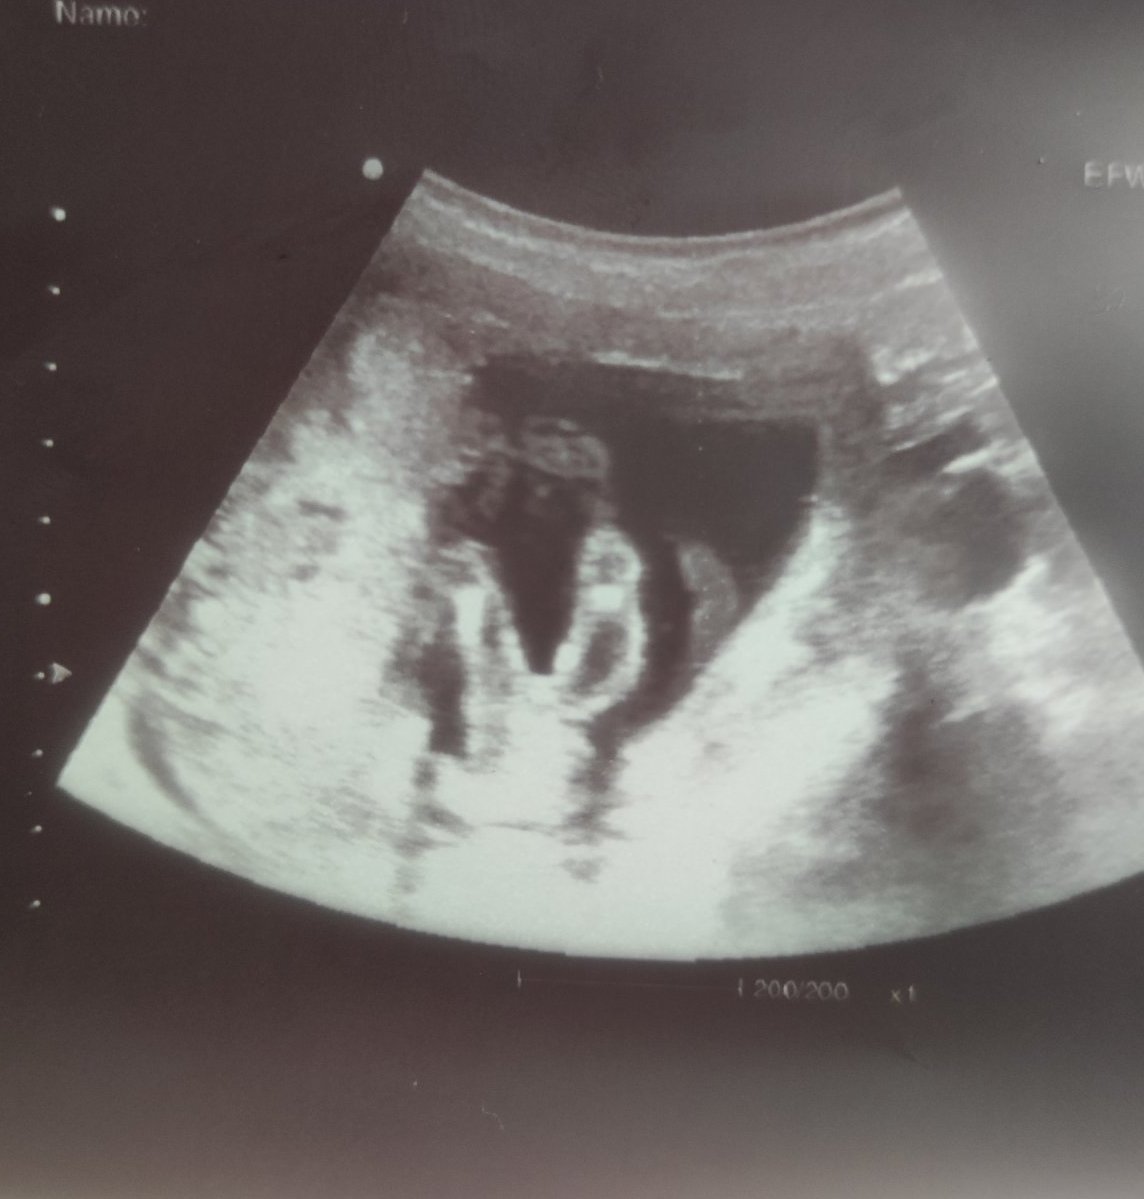

Здравейте февруарски мами!!❤️ Днес ми беше прегледа и очакваме 99.9% момиченце🩷🩷🩷🥳 много съм щастлива👣🥰 Видяха се срамни устни и малката си застана точно за да и направим една фотосесия между крачетата 😁🌼🌼🌼